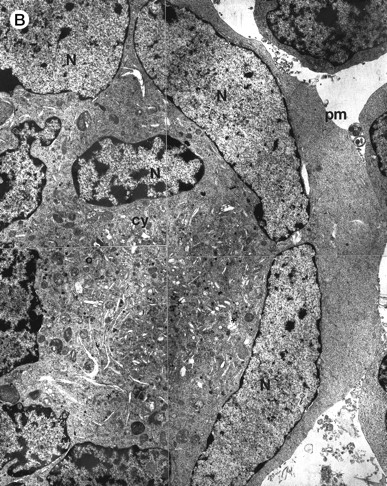

Morphologic examination of syncytia in HHV-7–infected SupT1 cultures (8 day pi) by light (A) and electron (B through E) microscopy. (A) Field with three syncytia and various single cells. (B) Multinucleated syncytium with an intact morphology. (C) Particular of a necrotic syncytium with vacuolized cytoplasm and initial discontinuation of the plasma membrane. Also note the lack of nuclear chromatin condensation. In (B) and (C), virions appear as dark points (asterisks). (D) Ringed nucleocapsids with an electron-dense core in the cytoplasm of a necrotic syncytium. (E) Particular of a syncytium in advanced stage of necrosis (bottom left), releasing mature virions (asterisks) in proximity of an intact cell (top right). N, nucleus; cy, cytoplasm; v, vacuole; pm, plasma membrane. Original magnifications: (A) ×400; (B and C) ×6,000; (D) ×36,000; and (E) ×7,000.

As expected,1,2 7 the morphologic examination performed at light microscopy showed the presence of giant multinucleated syncytia (Fig 2A). Because in this group of experiments the viral inoculum was represented by HHV-7–infected SupT1 cells, syncytia were already present at day 0 of infection, but their number progressively increased with the time of infection (data not shown).

At ultrastructural examination, a significant fraction of syncytia still maintained an intact appearance with little loss of cytoplasmic and nuclear organization despite the presence of numerous virions in the cytoplasmic compartment (Fig 2B). Although cytoplasmic virions were also observed in single cells, all syncytia invariably contained large amounts of typical herpesvirus nucleocapsids, which appear as single, ringed particles with an electron-dense center representing the core.27 28

However, most syncytia exhibited a vacuolized cytoplasm and discontinuation of the plasma membrane with lack of chromatin condensation, which are considered typical ultrastructural features of necrosis (Fig 2C). The morphologic features of necrosis were always associated with the presence of nucleocapsids in the cytoplasm (Fig 2D) and often with the release of mature virions in the extracellular space (Fig 2E). To ascertain that the ultrastructural features of syncytia shown above were truly representative of HHV-7 infection, various syncytia obtained from two separate experiments were analyzed. The presence of large amounts of cytoplasmic virions was confirmed in all syncytia examined, strongly suggesting that these giant multinucleated cells represented the major source of viral particles in the culture. Moreover, the majority of syncytia showed morphologic evidences of necrosis, whereas less than 5% showed apoptotic features (Table 1).